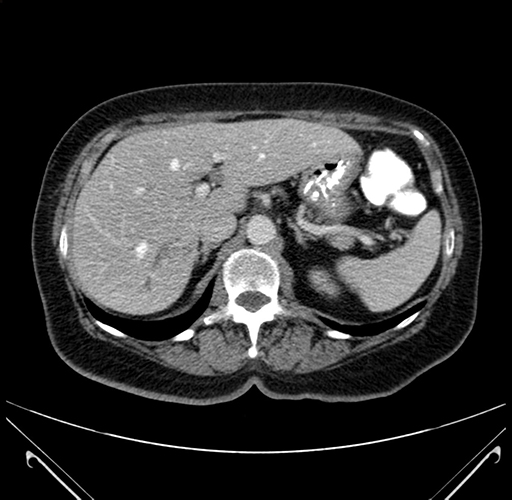

Axial Venous